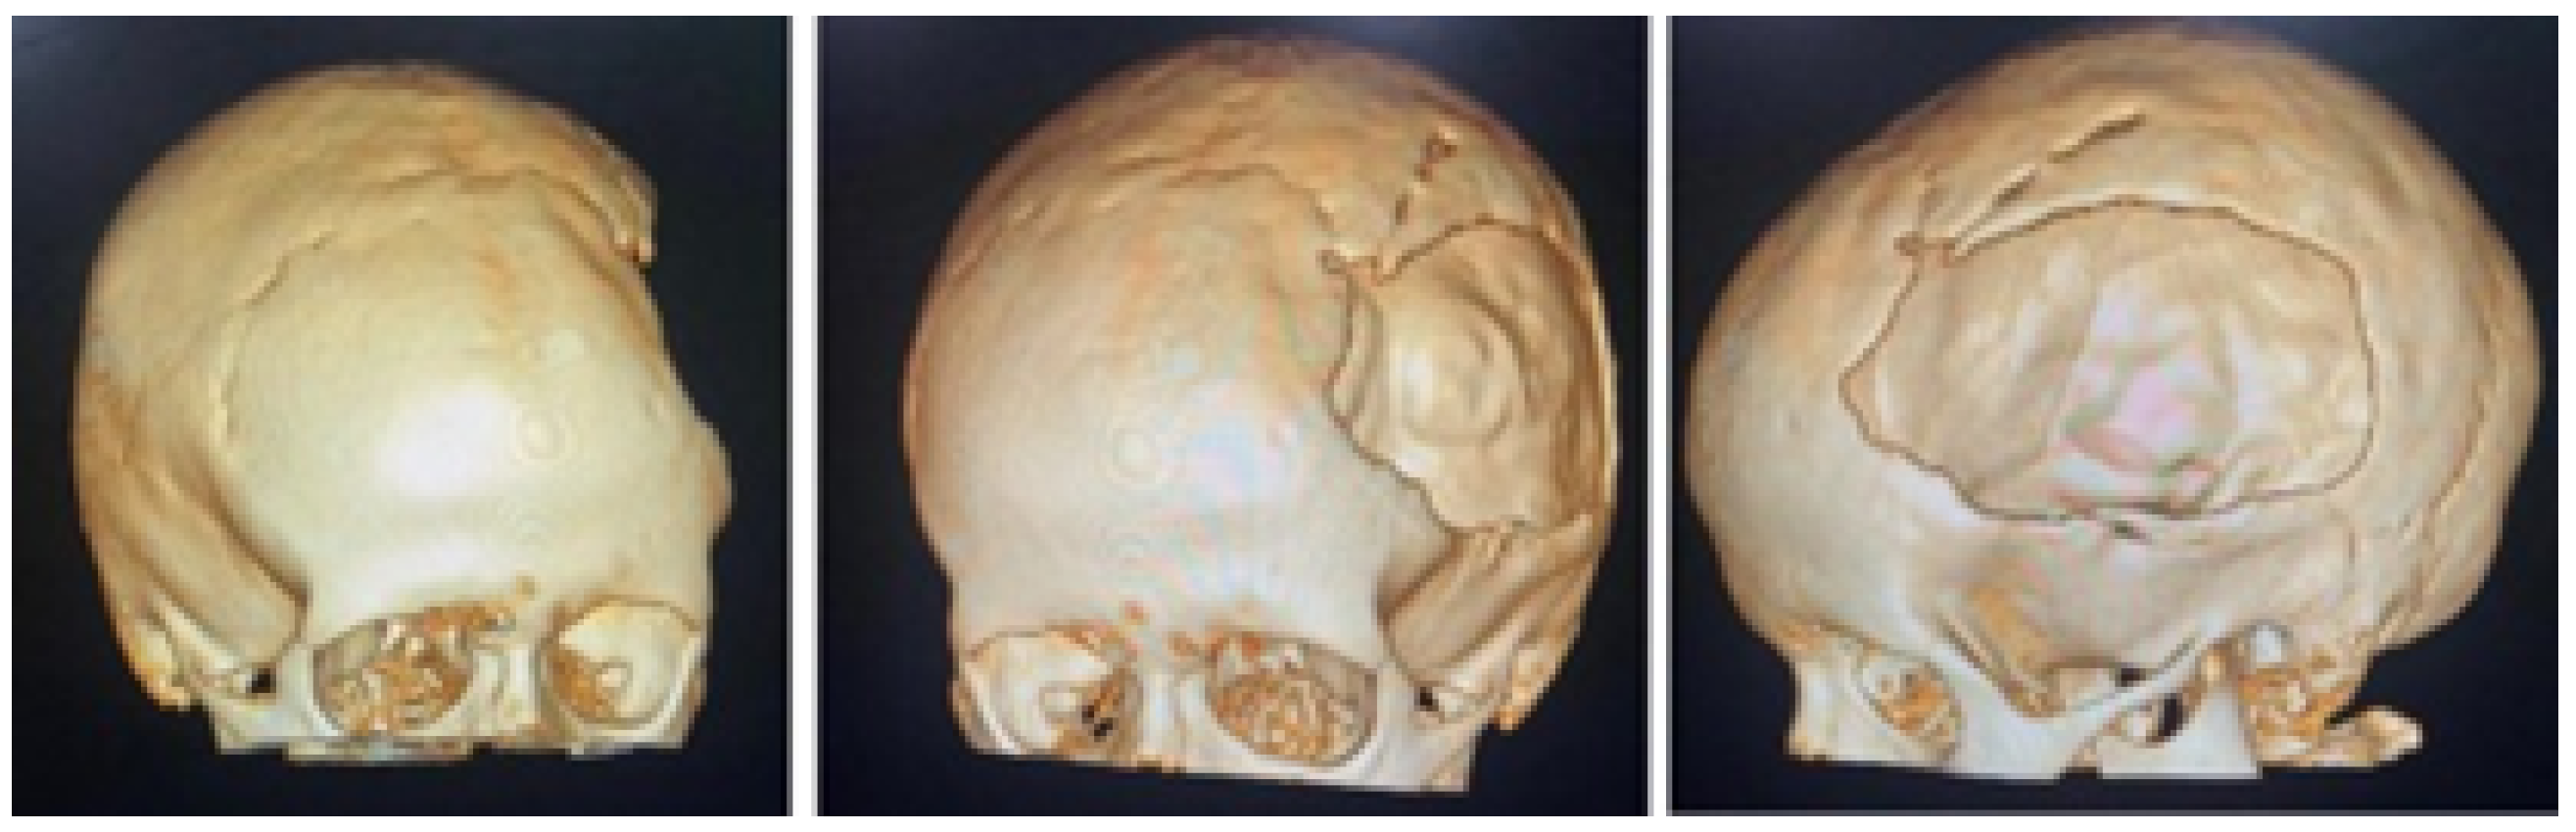

A 2-year-old female patient attended the consultation due to prominence in the temporal region as a result of cranioencephalic trauma. Physical examination revealed the prominence of the left temporal bone and ocular proptosis on the same side (see Figure 1). A computerised axial tomography (CAT) with three-dimensional reconstruction revealed a solution of bone continuity in the orbital roof and region of the left temporal squama, with front-orbital and temporal encephalocele (see Figure 2).

The defects identified were corroborated by both the patient’s medical history and physical examinations, as well as by tomography. The tomographic images were then segmented to reconstruct the left temporo-parietal cranial bone tissue. The density of compact cranial tissue was established using a range of 180 to 2000 HU (see Figure 3 and Figure 4).

Figure 2. Computed tomography (CAT). Left temporoparietal cranial defect, solution of continuity in the roof of the orbit and temporoparietal region.

Figure 3. Selection of the HU intensity (corresponding to the necessary bone density) from the tomographic image.

Figure 4. Bone segmentation of the anatomical model with the cranial defect.